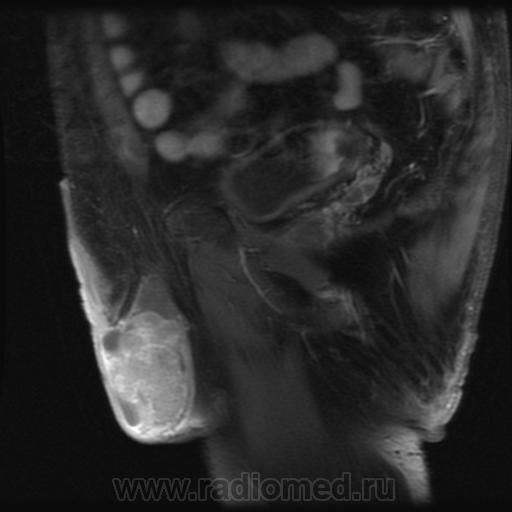

семинома?

Считаю, что семинома - не самый вероятный вариант, т.к. структура опухоли достаточно неоднородная, есть распространение на придаток и границы четкие.

Могу предположить, неоплазию правого яичка.

Я в заключении вынес на первый ряд карциному яичка.

"Мужчина, 60 лет. Около 3 месяцев назад появился дискомфорт в области мошонки, увеличение правого яичка."